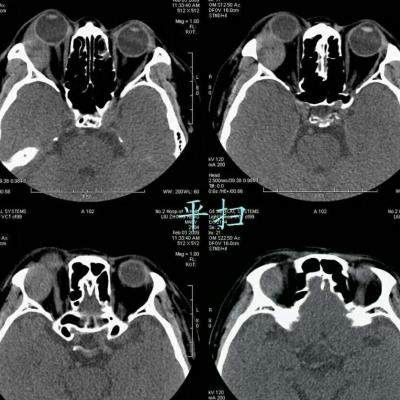

女,54岁,头痛头晕月余,无眼部症状及视力异常。 影像表现:右侧眼球后方占位病变,考虑海绵状血管瘤可能性大,鉴别:视神经鞘瘤、脑膜瘤及炎性假瘤。 病例点评:眼眶内血管瘤是较常见的良性肿瘤,其中以海绵状血管瘤最常见。可发生于任何年龄,主要表现为眼球突出及偏位,在低头或哭泣时可有突眼加重。可经眶缘触及具有压缩性的肿块。视力损害多较缓慢。肿块大多位于肌锥内,其次为肌锥外,平扫呈边界清楚的圆形、卵圆形或分叶状肿块,增强扫描呈缓慢进行性显著强化为其特征性表现。